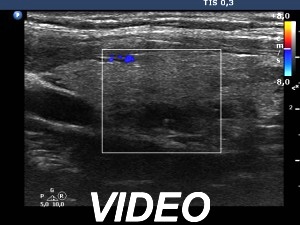

Ultrasonography. The thyroid was composed of numerous discrete lesions of various echogenicities. There was a partly cystic nodule in the upper-ventral part of the right lobe. The left lobe contained several cystic areas having comet tail artifacts.